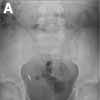

The patient is an 8-year-old girl with a history of asthma and developmental delay. She complained of hip pain, and her pediatrician referred her to a pediatric orthopedist for consultation. Hip x-ray films were ordered; they revealed 3 round beads in the child's appendix (A). The child's mother remembered that the child had been chewing on a beaded bracelet 1 to 2 months before the films were taken.

The child's hip pain subsequently resolved and the results of an abdominal examination were normal, according to John Harrington, MD, Michael Morris, MD, and Whitney McBride, MD, at the Maria Fareri Children's Hospital at New York Medical College in Valhalla, NY. Nevertheless, the child underwent elective appendectomy to remove the beads (B). She recovered uneventfully.